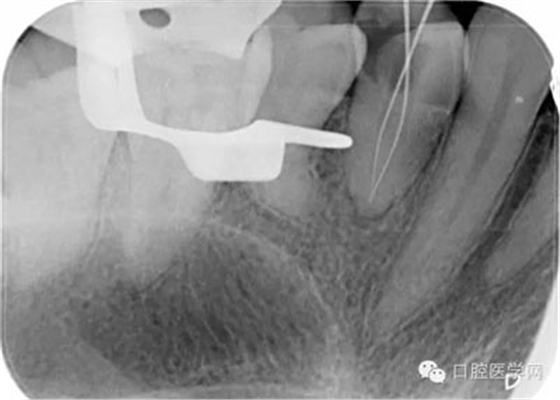

第五步:確定根管長度,臨床上常用方法為根測+X片+吸潮紙尖法。

根測法:用不銹鋼K銼插入根管直至有阻力部位,夾入根管測量儀器測量,一般距離根尖顯示0.5MM為工作長度。

X片法:X線片上可以清楚看到根管銼插入根管的深度,但因看到的是解剖性根尖,而根尖孔大多數(shù)開口于側(cè)方,所以X線片 到達根尖時,實際是超出了。數(shù)據(jù)顯示根尖孔距離根尖可以從0.5mm-3mm之間。

(我的助手是拍個X片就像是段譽練的六脈神劍,時靈時不靈。不過這張片,我還是覺得美呆了。)